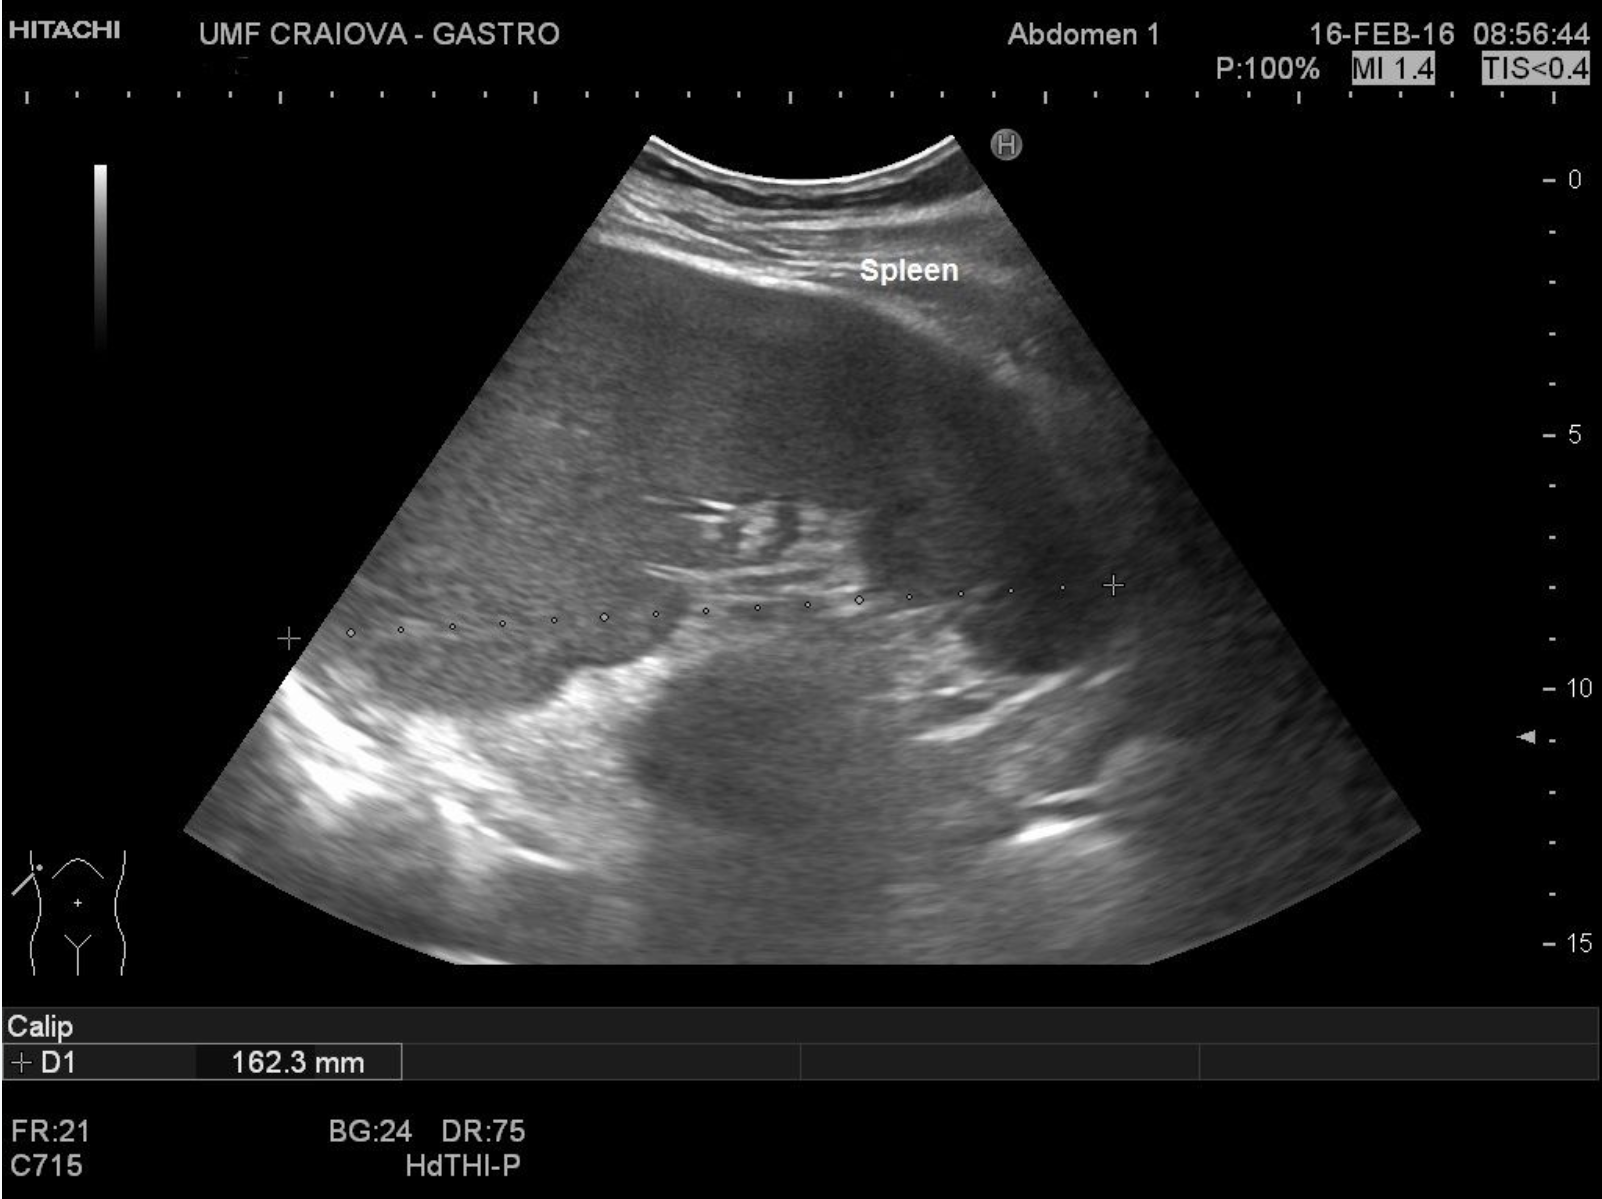

Splenomegaly [1 image] Categories BASIC ULTRASOUND IMAGESSpleenSplenomegaly TITLE: Splenomegaly DESCRIPTION: Long axis > 13 cm, around 16 cm EMAIL CONTACT:constantinescu.codruta@yahoo.com KEYWORDS:spleen ultrasound, splenomegaly Related postsJanuary 5, 2021Walled-off pancreatic necrosis [2 images]Read more